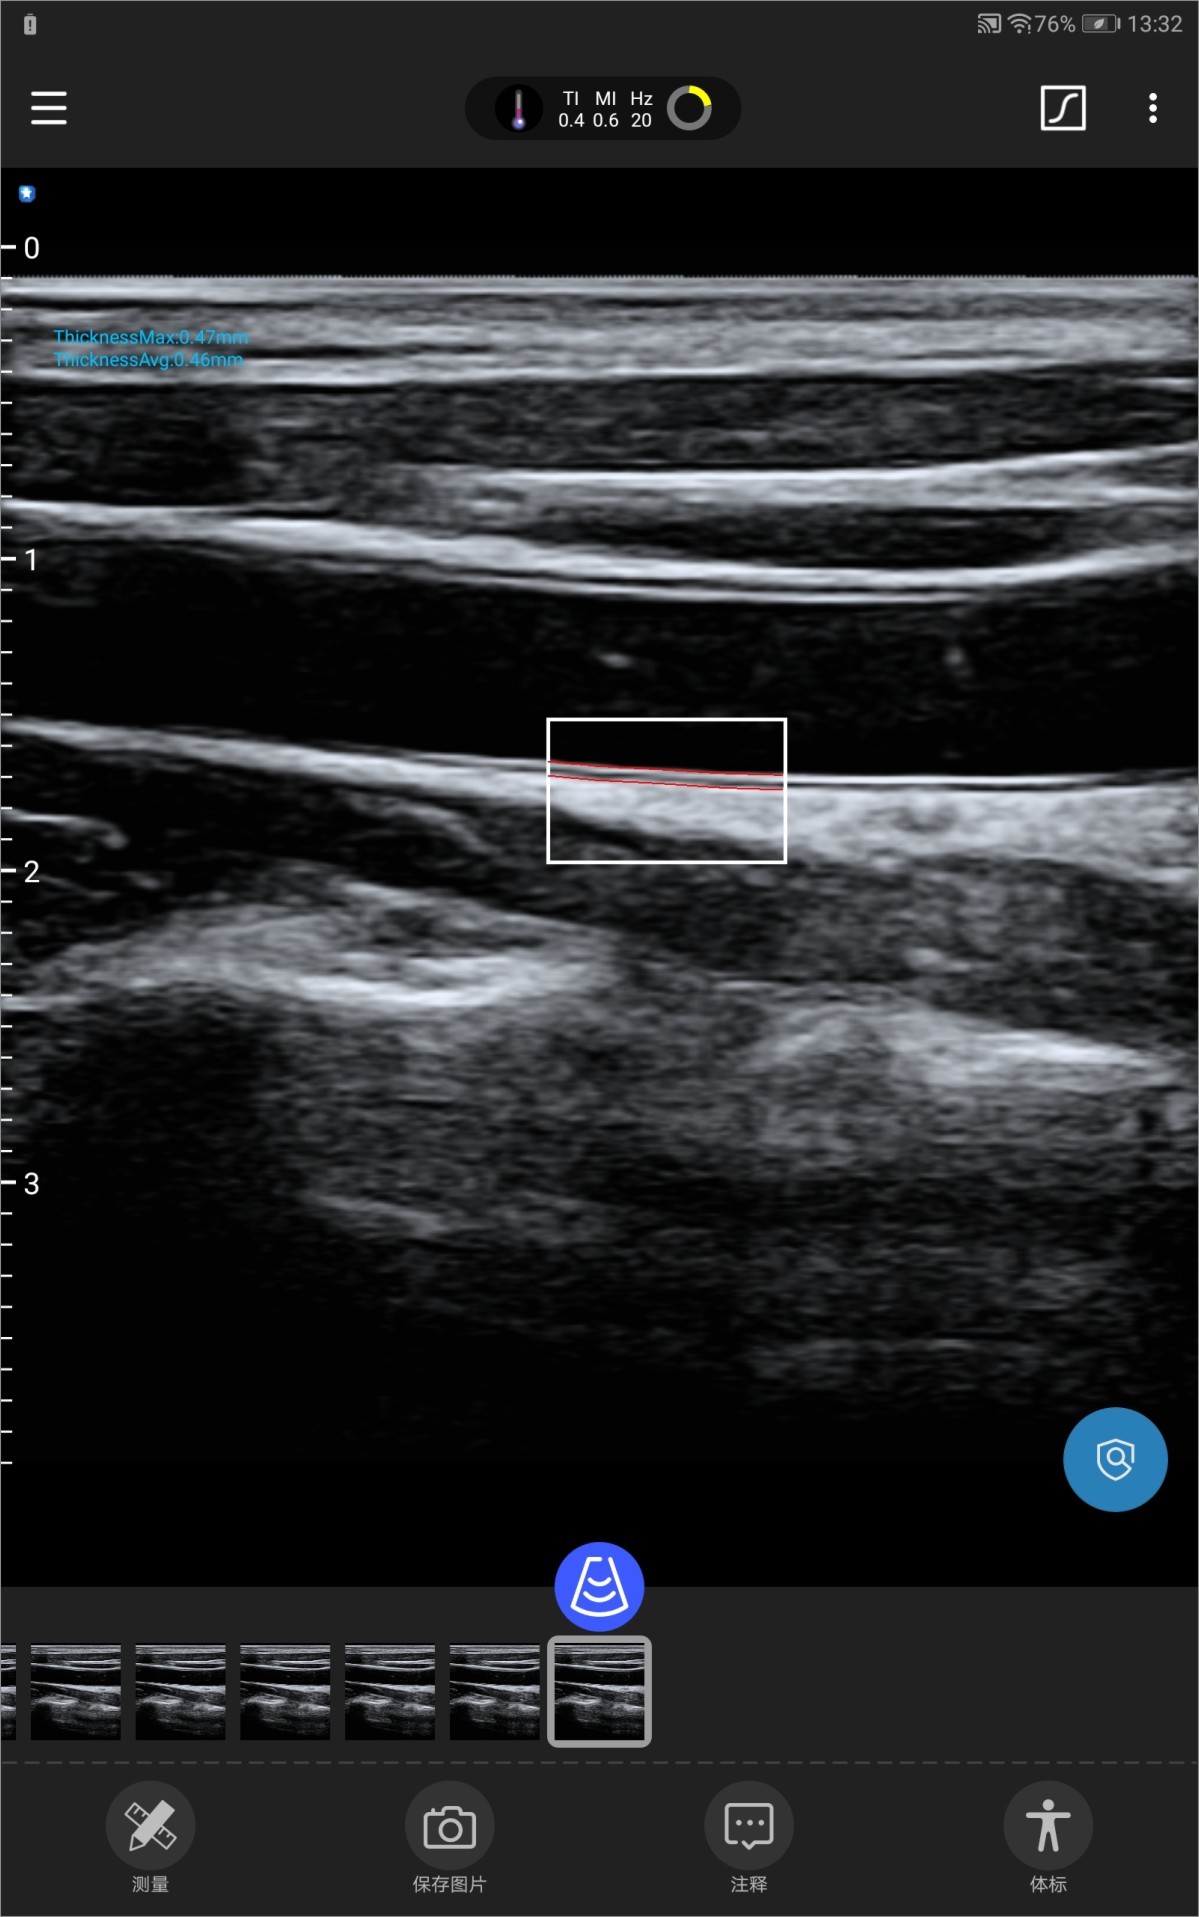

Autorreconocimiento y automedición de IMT